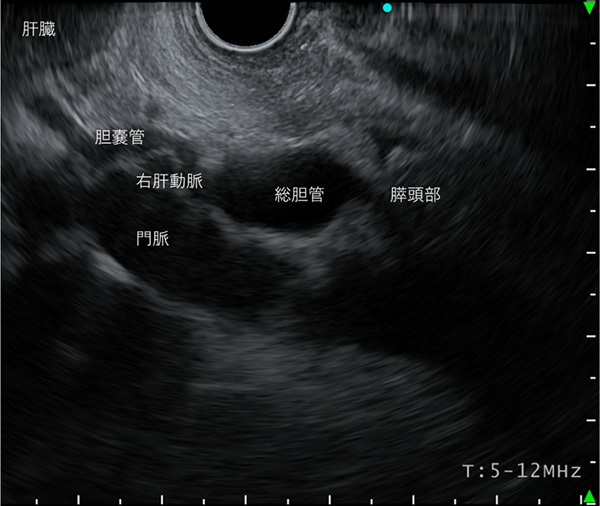

〈十二指腸球部操作による観察〉

肝門部からVater乳頭まで観察します。特にこの領域は、胆管の観察に充填をおきます。

胆管を肝門方向に観察していくと、胆嚢管及び胆嚢の描出が可能となります。